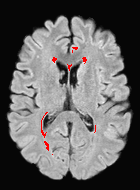

Patch size is another important parameter of the network. In computer vision applications such as object detection, usually a whole 2D image is used as a feature. However, full 3D medical images can not typically be used because of memory limitations. Fig. 4 shows examples of lesion memberships obtained with different sized 2D patches. As the patch sizes increases, the false positives that are mostly observed in the cortex tend to decrease. Fig. 5 shows a plot of Dice and LFPR with various patch sizes, ordered from left to right according to their increasing size. Note that smaller patches ( to ) produced significantly lower Dice and higher LFPR compared to other patches (), as seen from the memberships in Fig. 4. Also some of the highest Dice and lowest LFPR were observed for patches with large in-plane size, i.e., , , and . It was observed in Fig. 5 that there is no significant difference between Dice coefficients for , , or , but LFPR of both and are significantly lower than that of (). We chose as the optimal patch size. Other choices of smaller and patches (not shown) yielded worse results. Note that although training was performed with different patch sizes, the memberships were generated slice by slice, as the trained model consisted only of convolutions and did not need any information about patch sizes.

In our experiments, we used large 2D patches similar to Ghafoorian et al. (2017b), in comparison to isotropic 3D patches as used before, e.g., in Valverde et al. (2017), in Wachinger et al. (2017), and in Kamnitsas et al. (2017). The rationale behind using large anisotropic patches is twofold. First, experiments with full 3D isotropic or patches showed little or no improvement in Dice and led to increased false positives, with memberships similar to the one with patches, as shown in Fig. 4. Larger isotropic patches, e.g. or , showed inferior segmentation, and in some cases, optimization did not converge. The reason is that the FLAIR images in the test datasets had inherently low resolution in the inferior-superior direction, mm and mm compared to in-plane resolution of mm. Therefore 2D axial patches capture the high resolution in-plane information that represents the original thick axial slices. Second, the lesions are usually focal and small in size, unlike other brain structures. Therefore a very large isotropic patch around a small lesion can include superfluous information about the lesion, which can increase the amount of false positives. Note that with in more recent studies employing high resolution 3D FLAIR sequences, it is trivial to extend the algorithm to accommodate for 3D patches.